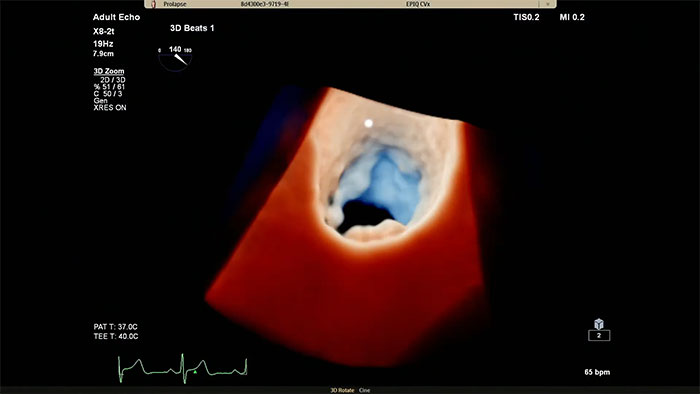

Rapidly acquire LAA orifice measurements in both traditional rendering or in TrueVue Glass rendering, with 3D Auto LAA